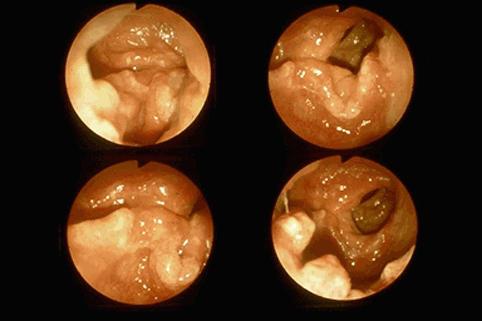

Rectal mucosal prolapse syndrome with various morphological changes.

Inflammatory or ulcerative disease / lesions/Rectal mucosal prolapse syndrome

Large intestine(Colon)/Rectum

Endoscopy